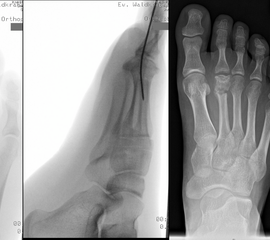

Schneiderballen: MT V Osteotomie

Diese Osteotomie ist indiziert bei stark lateralisierten MT V Köpfchen wie es nicht selten in Kombination mit einem Hallux valgus, einem Ballen-Hohlfuß oder Klumpfuß vorkommt (Abb. 25).

Abb. 25: Prominentes MT V Köpfchen, eine sogenannte Schneiderballen-Deformität.

Dementsprechend führen wir die MT V Osteotomie häufig als Kombinationseingriff durch. Sie kann subcapital im Sinne der Kramer-Osteotomie oder adduzierend am Schaft durchgeführt werden (Abb. 26).

Abb. 26 a-e: adduzierende Osteotomie. (a) Fuß präoperativ d.p. und (b) als Schrägaufnahme. Im Schrägbild gut sichtbar die subluxierte 5. Zehe. (c) intraoperative Aufnahme der MT V Schaftosteotomie. (d) Fuß postoperativ d.p. und (e) als Schrägaufnahme.